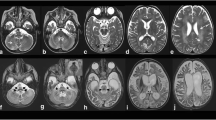

MRI and CT investigations showed mild involvement of the periventricular white matter (high T2 signal), without clear effects on subcortical tissue (Fig. 1). No local calcifications were evident at these sites. Ventricles and sulci were within normal size limits.

At the level of the basal ganglia, we found symmetric T1-shortening involving the head and body of the caudate nuclei, pallidus, putamen, and posterior-medial thalami (Fig. 2). The T2*GE sequence and a CT scan confirmed the presence of diffuse calcifications, particularly in the bilateral globus pallidus (Figs. 3, 4), where the T1-SE and T2-SE signal was hypointense. Some thin linear calcifications extended from the caudate into the semioval centre and towards the cortex, following vessels and cortical projections. The brainstem and the cerebellar white matter were not affected.